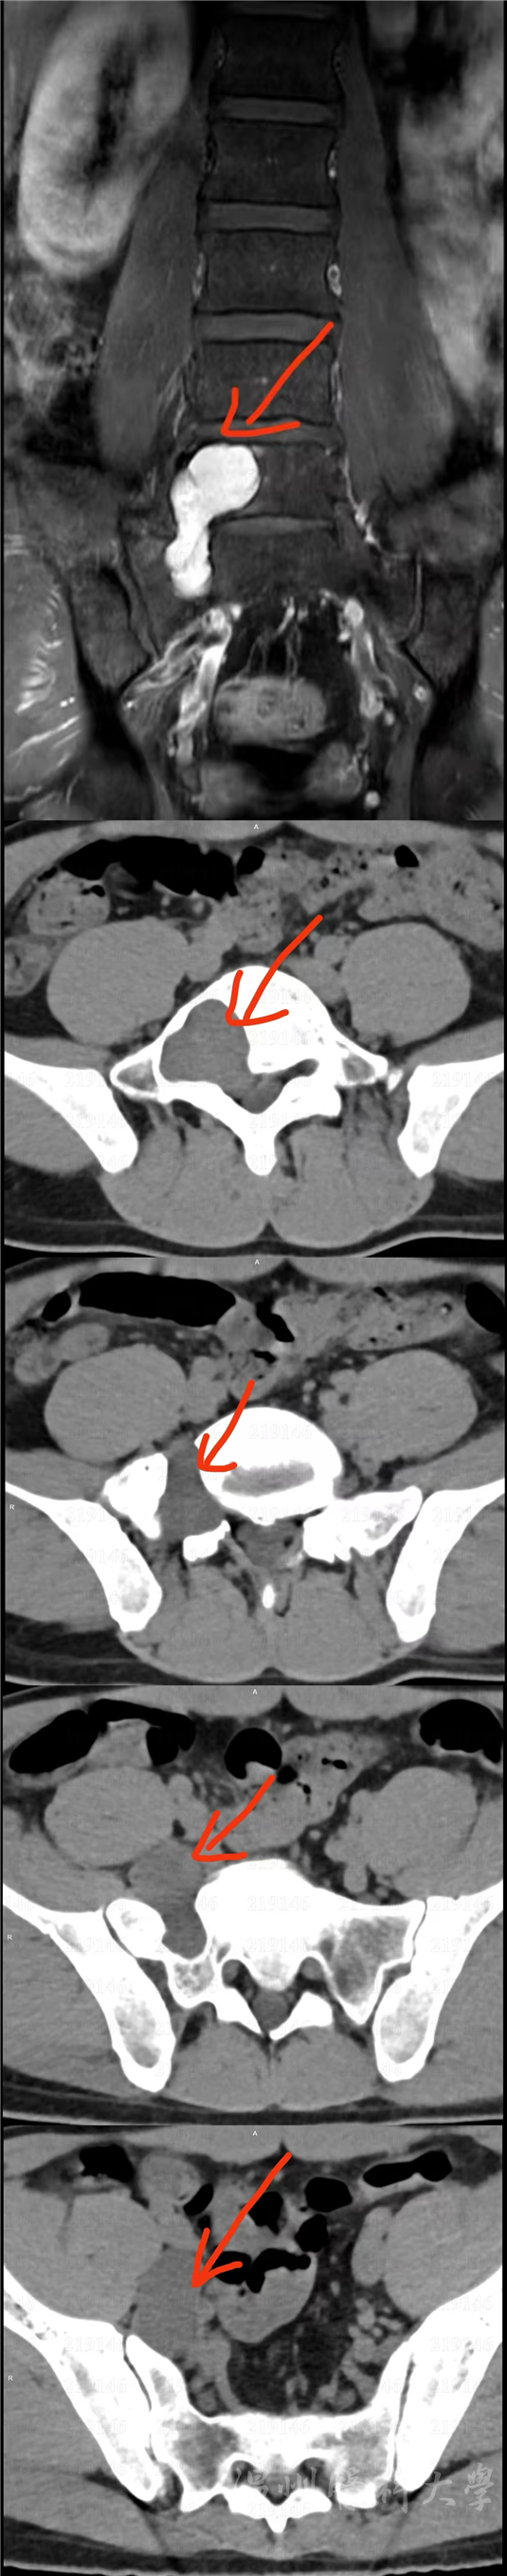

疾病的起点,是持续五年的“反复腰腿痛”。对这位中年男性患者而言,这不仅是身体的负担,更是精神的煎熬。在当地医院检查发现,其腰骶部存在占位性病变,初步诊断为L5/S1右侧椎间孔神经鞘瘤,且肿瘤已侵犯L5椎体。

该肿瘤位置极为凶险,深藏于骨盆深处,紧贴控制下肢感觉与运动的关键神经根,并与脊柱结构紧密相连。这一区域被视为手术“禁区”,稍有不慎就可能导致大小便功能障碍或下肢瘫痪,手术风险极高。为寻求一线生机,患者选择转至温州医科大学附属第二医院。

术前讨论中,专家团队对影像资料进行层层剖析,精准构建肿瘤与周围神经、血管、骨骼的空间关系。大家一致认为,手术需在完整切除肿瘤的同时,最大限度保护神经功能,这对团队协作提出极高要求。

与此同时,肛肠外科团队经腹腔入路建立腔镜操作通道,在高清视野下精细分离肿瘤与直肠、骶前筋膜及盆腔神经血管的粘连,实现肿瘤的精准游离。在麻醉与护理团队全程护航下,前、后路手术顺利“会师”,肿瘤被完整切除。手术出血少、创伤小,术后病理证实为神经鞘瘤。患者腰腿痛症状消失,未遗留神经功能后遗症,实现精准治疗与快速康复。